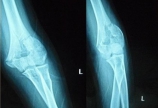

肱骨髁间骨折

患者杨某,女,18岁,因摔伤致左肘部疼痛、肿胀活动不利2小时,急诊以“左肱骨髁间粉碎性骨折”收入院。